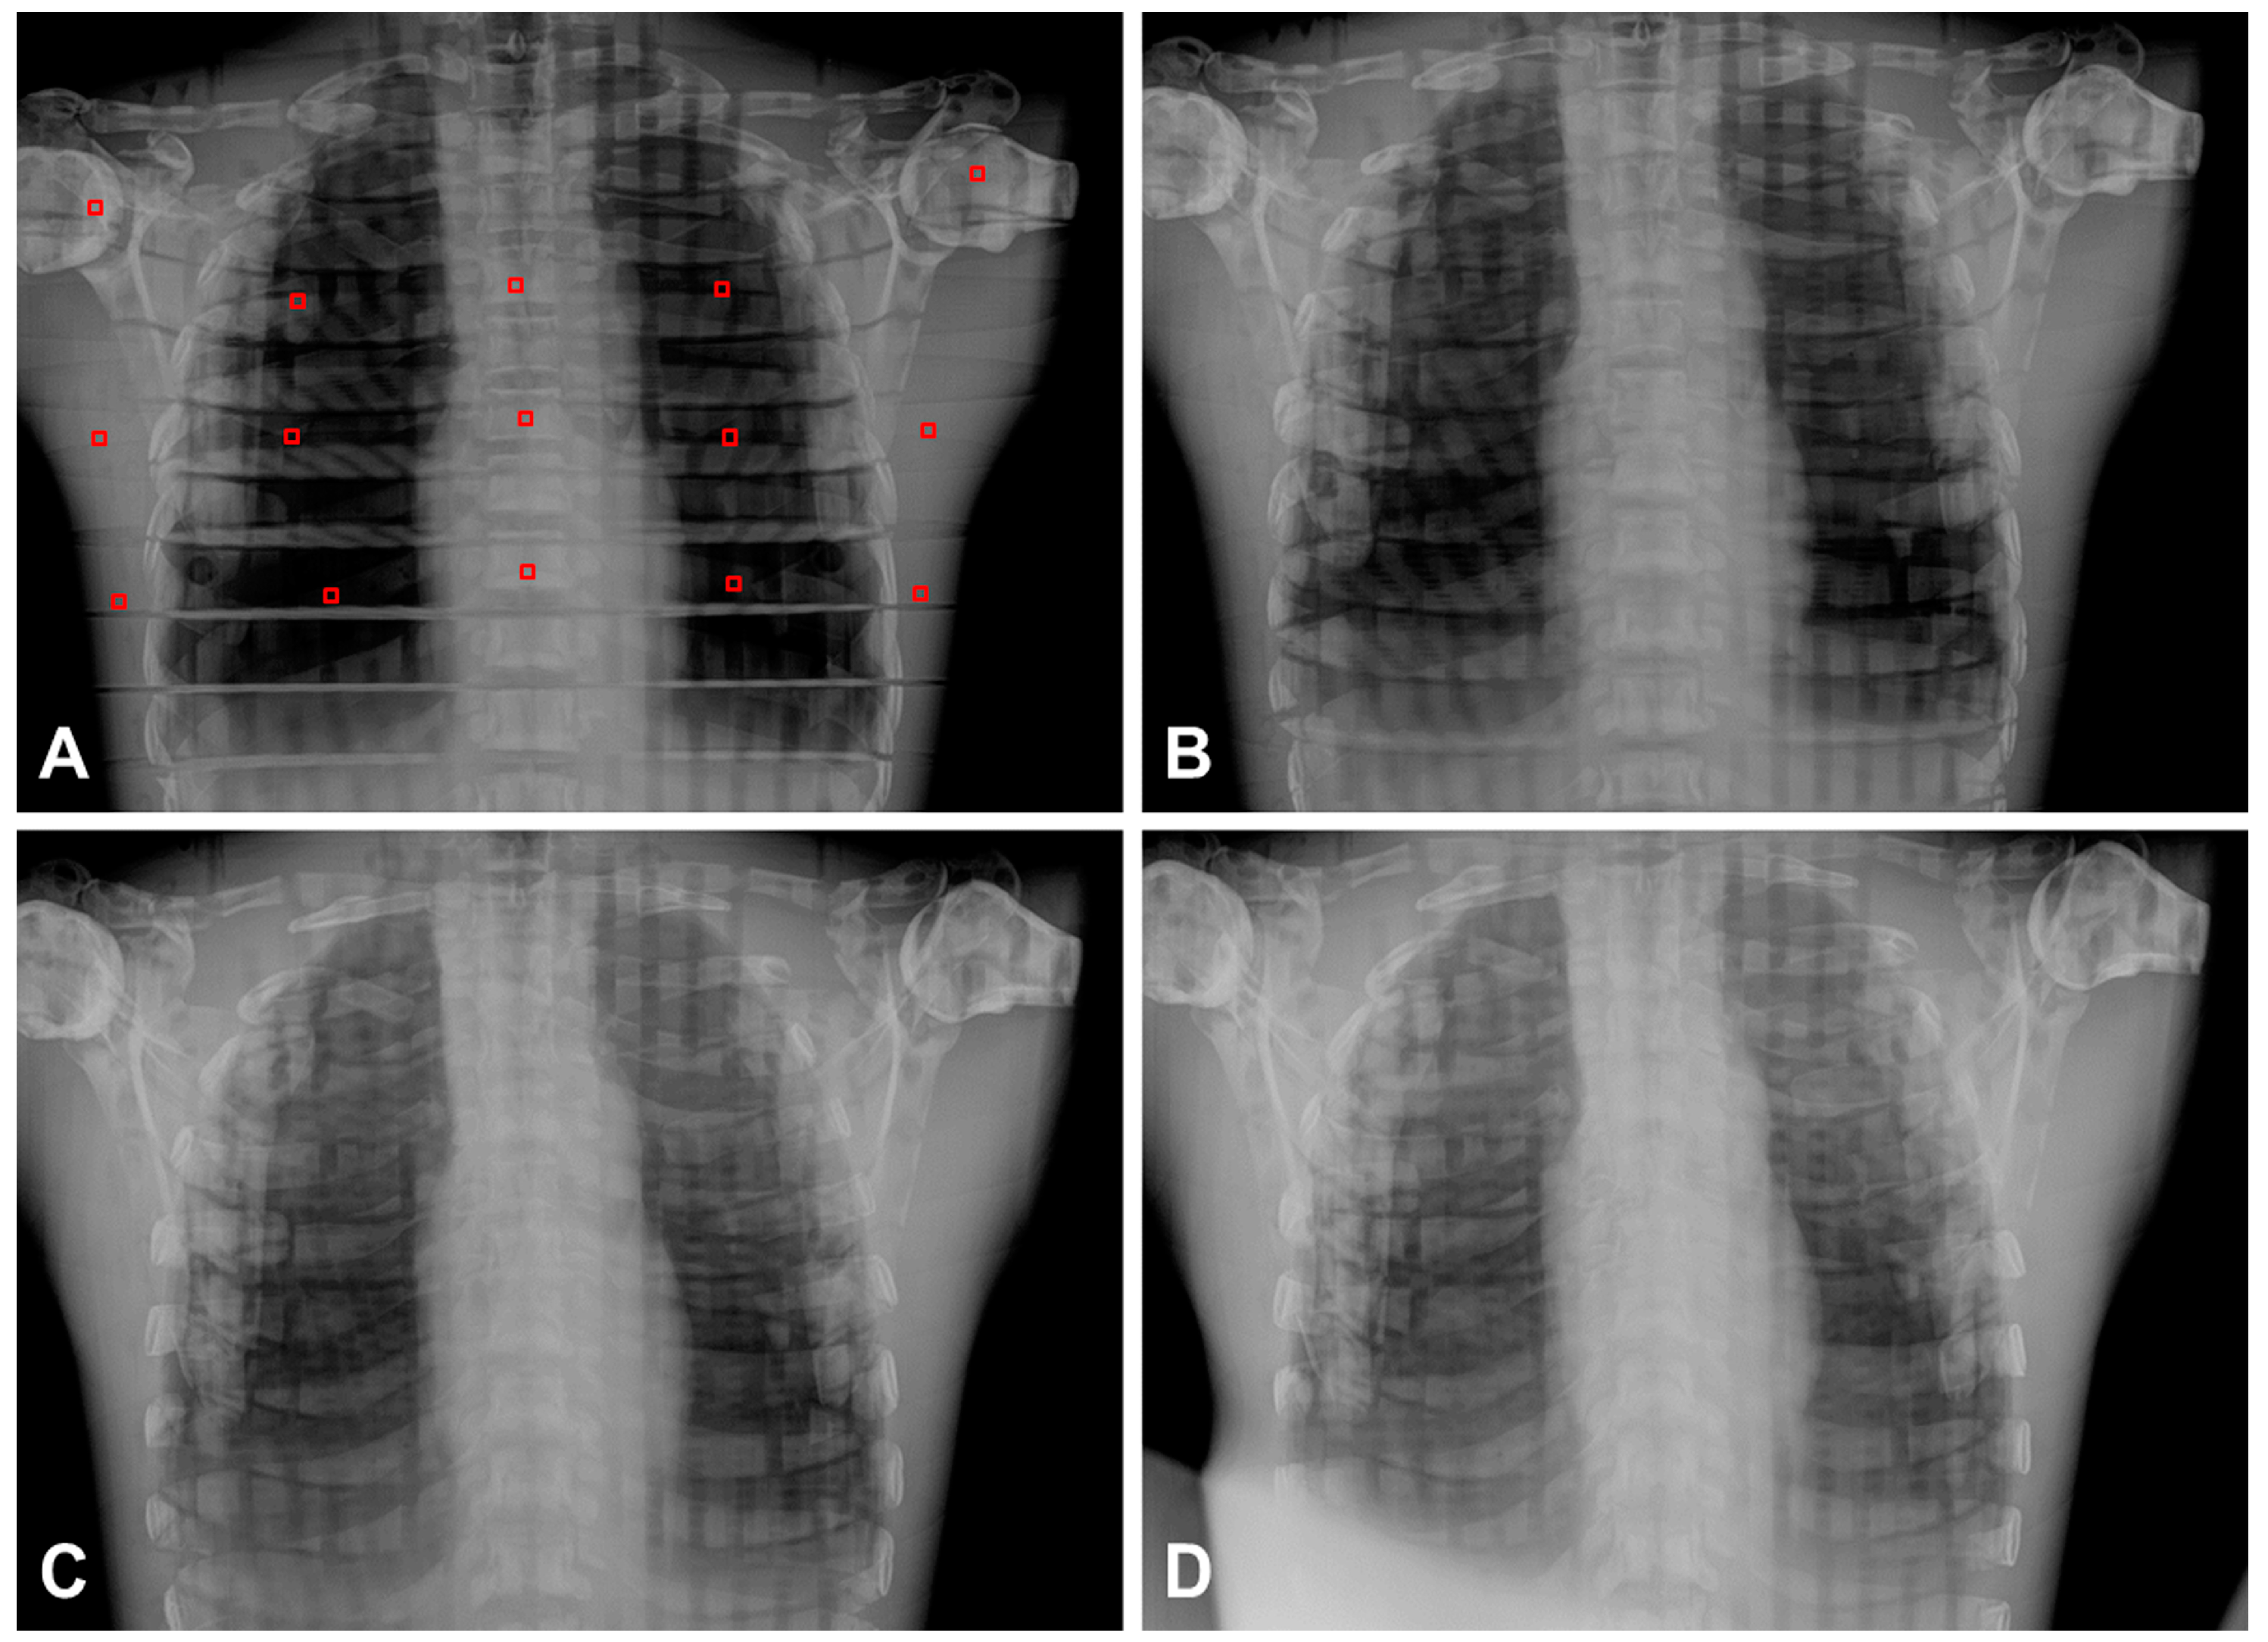

3.3. Chest Radiographic Study According to Different Angles for Clinical Application

| Angle Degree | 0° | 10° | 20° | 30° | p-Value * | |

|---|---|---|---|---|---|---|

| Value | ||||||

| SNR | 408.7 ± 160.0 | 408.8 ± 157.8 | 428.0 ± 176.3 | 463.4 ± 155.9 | 0.082 | |

| CNR | 82.3 ± 23.0 | 100.0 ± 30.9 | 102.8 ± 33.1 | 98.2 ± 28.8 | 0.114 | |

| Distortion † | ||||||

| CTD (size, mm) | 101.9 ± 0.3 | 104.4 ± 0.3 | 106.6 ± 0.4 | 107.5 ± 0.3 | <0.001 abcdef | |

| (deformity, %) | (100.0%) | (102.5%) | (104.6%) | (105.5%) | ||

| TTD (mm) | 278.0 ± 0.3 | 278.5 ± 0.1 | 278.7 ± 0.1 | 279.4 ± 0.3 | <0.001 abcdef | |

| (%) | (100.0%) | (100.2%) | (100.3%) | (100.5%) | ||

| TLD (mm) | 250.2 ± 1.0 | 260.7 ± 1.3 | 266.3 ± 1.3 | 273.7 ± 1.4 | <0.001 abcdef | |

| (%) | (100.0%) | (104.2%) | (106.4%) | (109.4%) | ||

| Visibility ‡ | ||||||

| Border of Heart | 1.67 ± 0.52 | 2.17 ± 0.75 | 2.50 ± 0.55 | 3.00 ± 0.00 | 0.044 bce | |

| Clavicle | 1.00 ± 0.00 | 1.33 ± 0.52 | 1.50 ± 0.55 | 1.83 ± 0.41 | 0.110 | |

| 1st Rib (Rt-side) | 1.00 ± 0.00 | 1.33 ± 0.52 | 1.50 ± 0.55 | 1.67 ± 0.52 | 0.292 | |

| 5th Rib (Rt-side) | 1.33 ± 0.52 | 1.67 ± 0.52 | 2.33 ± 0.52 | 3.00 ± 0.00 | <0.001 bcdef | |

| Scapula | 1.17 ± 0.41 | 1.50 ± 0.55 | 1.67 ± 0.52 | 2.33 ± 0.52 | 0.032 cef | |